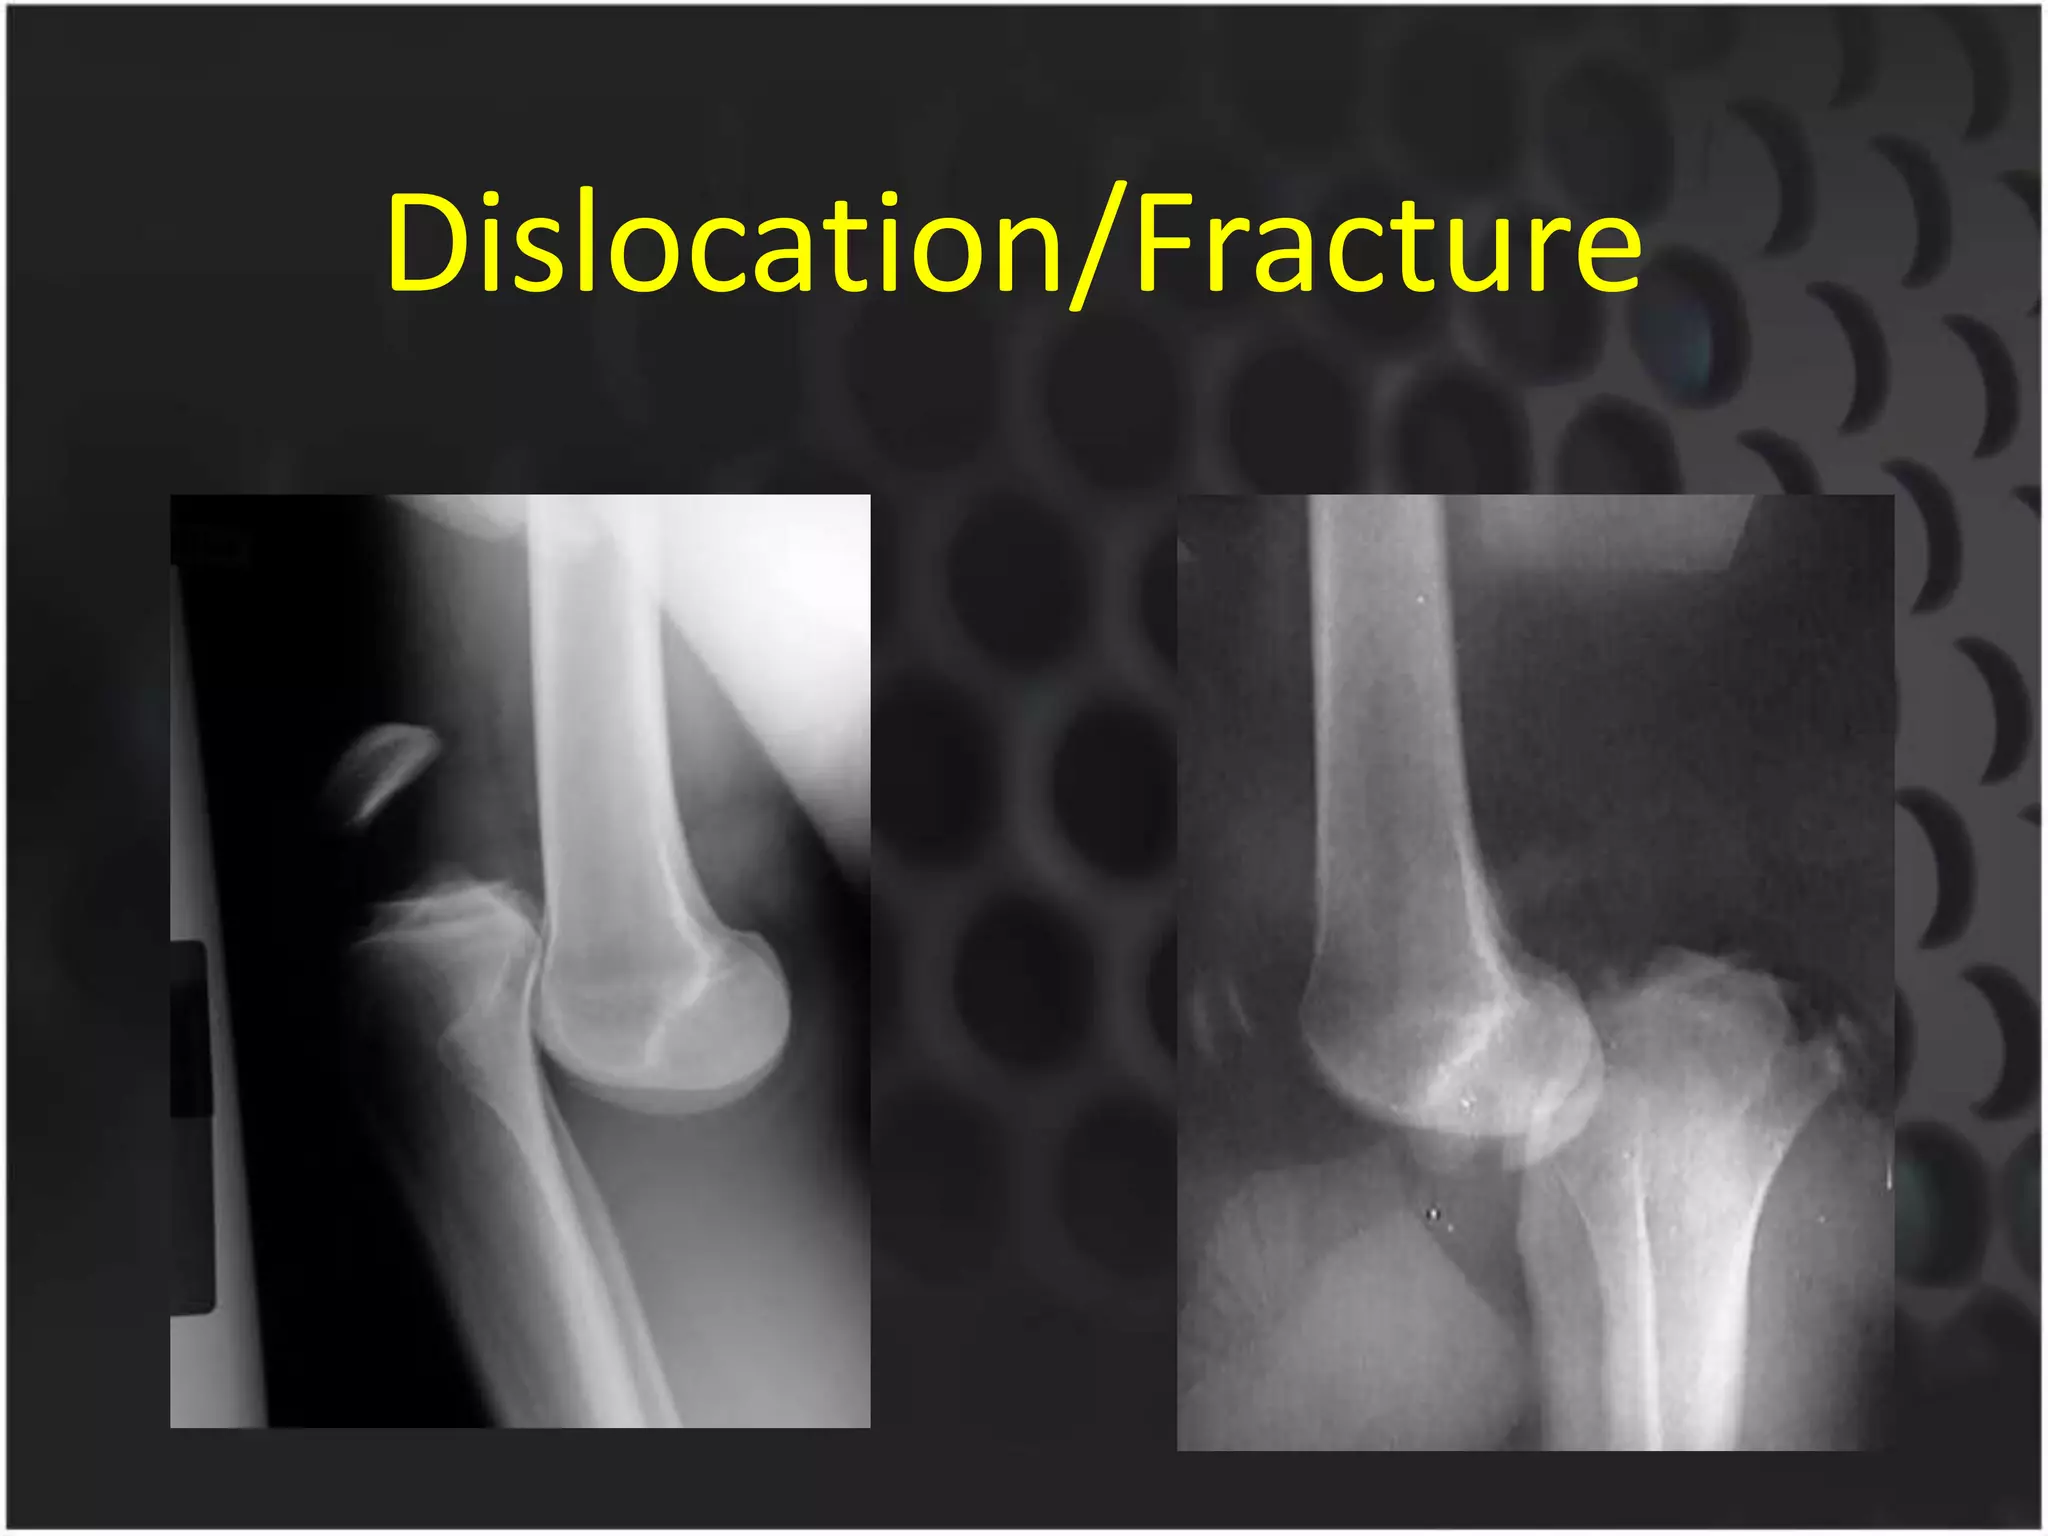

This document discusses trauma to the pelvis, hips, knees, ankles, and feet. It covers anatomy, imaging techniques, and types of fractures and dislocations that can occur in these areas. The types of fractures discussed include pelvic ring fractures, acetabular fractures, and fractures of the femur, tibia, fibula, and bones of the foot. Imaging views used include AP, inlet, and outlet views of the pelvis. Dislocations and fractures of the knee, ankle, and foot joints are also examined.